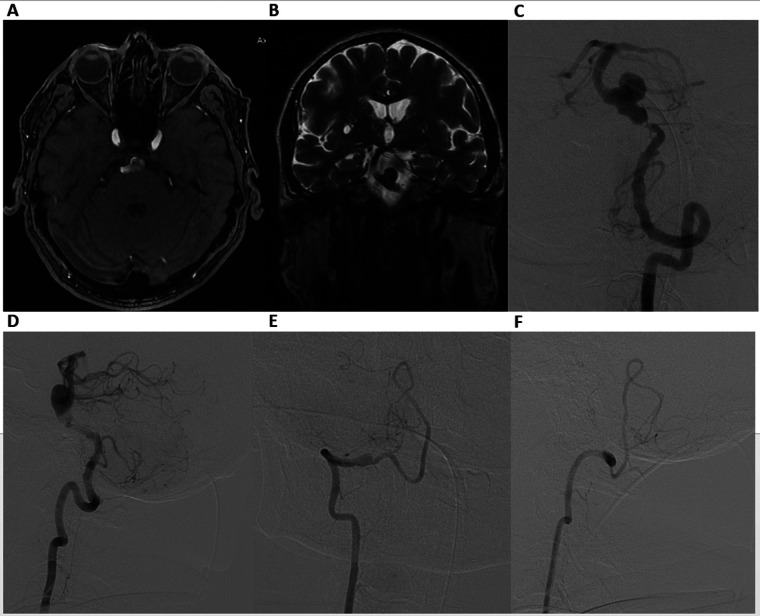

背景:复杂基底动脉动脉瘤的治疗具有挑战性,因为其解剖位置较深,靠近关键穿动脉,并且其频繁的梭状形态和与长段狭窄或动脉粥样硬化改变有关。血管内分流已成为重要的选择;然而,它在大的和梭状的基底动脉动脉瘤中的应用是复杂的,因为装置错位、移动和不完全闭塞的风险。病例介绍:我们报告一例大基底动脉瘤伴严重动脉瘤前狭窄的病例,采用套筒式血流分流术治疗。在支架部署之前进行球囊血管成形术以优化血管直径,然后依次从远端到近端放置重叠的血流分流器。术后血管造影显示设备不稳定,需要在“支架内支架”配置中部署额外的分流器,以改善管壁的放置并防止迁移。这种方法导致持续的动脉瘤血栓形成和长期的血管通畅。结论:本病例说明了处理复杂基底动脉动脉瘤的技术挑战,并强调了辅助支架置入在稳定血流分流器中的作用。考虑到梭状形态、长段动脉受损伤、动脉粥样硬化改变和穿孔丰富的环境,以及需要套筒重建或辅助球囊血管成形术等技术挑战,仔细个性化的血管内策略对于提高手术安全性和实现高风险患者持久的动脉瘤闭塞至关重要。

Case presentation: We report a case of a large basilar artery aneurysm with severe pre-aneurysmal stenosis treated using a telescopic flow-diverter strategy. Balloon angioplasty prior to stent deployment was performed to optimize vessel diameter, followed by the sequential distal-to- proximal placement of overlapping flow diverters. Post-procedural angiography revealed device instability, necessitating the deployment of an additional flow diverter in a "stent-within-a-stent" configuration to improve wall apposition and prevent migration. This approach resulted in sustained aneurysm thrombosis and long-term vessel patency.